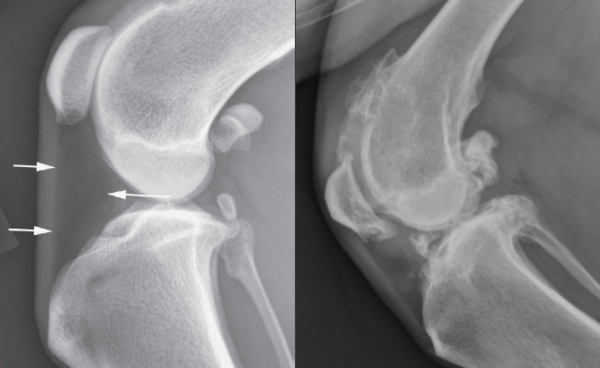

332b87321f0523a534b6e7c80a2bc1e1_1756779971_1805.png

좌측: 정상관절, 우측: 십자인대가 파열된 환자의 관절

왼쪽의 사진은 정상관절,

오른쪽의 사진은

십자인대 파열 환자의 관절입니다.

차이점을 구분 하시겠나요?

지속적인 무릎관절의 마찰로

뼈가 울퉁불퉁해질 뿐만 아니라

한번 유발된 퇴행성 관절염은

수술적으로 해결할 수 없어

더욱 큰 문제입니다.